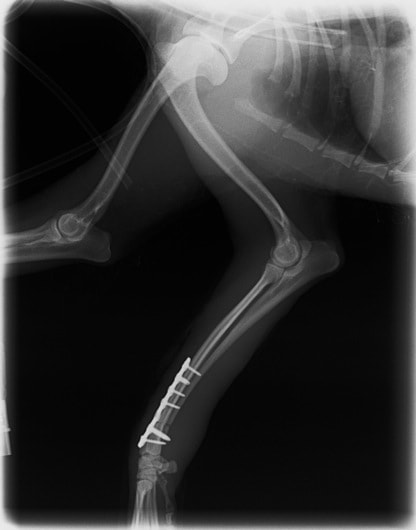

症例3:キルシュナーワイヤーのピンニングによる整復

ペルシャ猫 11ヶ月齢 雄

他院にて左大腿骨遠位の成長板骨折(salter-harrisⅠ型)が認められており、治療相談を目的として来院。当院にて、キルシュナーワイヤーを用いたピンニングにより骨折部位の整復を行いました。術後の経過は良好で、現在も経過観察中です。

術前レントゲン

術後レントゲン